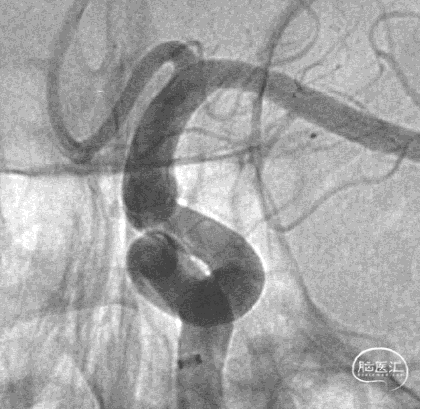

可见一小泡自动脉瘤瘤体上发出

瘤体最大径6.92mm

远端血管直径:3.28mm

近端血管直径:3.98mm

同侧A1可见一小瘤突起

Fastrack微导管到位

TB Plus 4/35